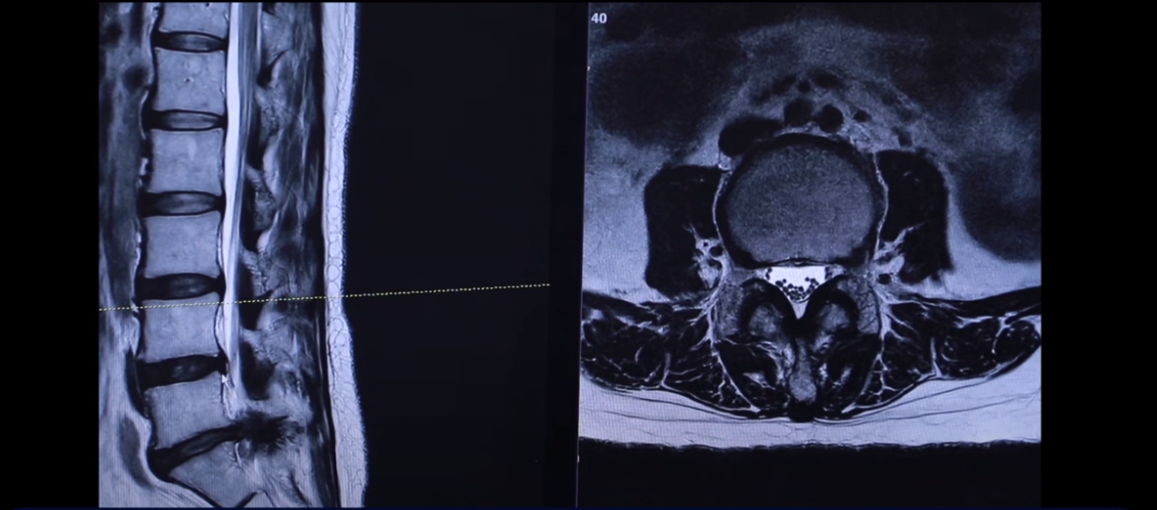

주사도 놔주지 않습니다. 주사가 전혀 의미가 없을 거라고 얘기하고 ‘무조건 수술을 해야 된다’ 이렇게 얘기를 듣습니다. 그런데 이분의 친언니 분이 있는데 그 친언니 분이 한 2년 전에 저희 모커리한방병원에서 허리디스크 파열로 치료를 받으셨습니다. 근데 친언니분도 MRI 디스크 터진 게 완전히 똑같습니다. 그분도 치료 후기를 이렇게 찍으셨는데요. 그분 MRI를 여기서 다시 한 번 보실까요?

이게 그 언니분 MRI인데 언니분도 5번 1번 정확히 왼쪽으로 터져 있습니다.

그래서 디스크가 유전이 관련돼 있다, 디스크란 질환이 그게 어느 정도 이런 걸 보면 알 수가 있습니다. 수많은 마디 중에 동생분도 이렇게 세 마디가 퇴행이 돼 있습니다. 맨 마지막 마디가 왼쪽으로 밀려나간 거 정확히 똑같습니다. 이분도 한 2년 전에 저희 병원에서 입원 집중 치료받고 완전히 좋아지셨습니다. 그래서 지금 일상생활 잘하고 계시고 이 치료후기 안에서 그 부분에 대해서는 동생분이 얘기를 합니다.